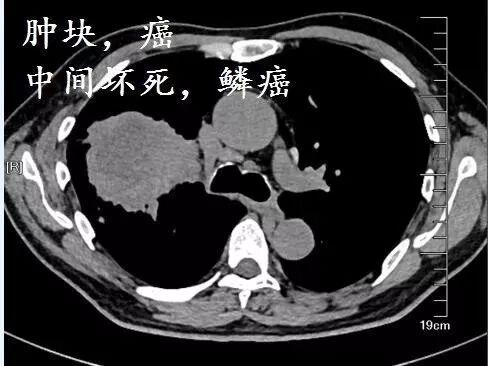

下面这个是什么?

首先,磨玻璃影,很可能是癌;假如里面有高密度的实性成分,则更可能是癌,并且,接近100%是腺癌

假如病理科报道:鳞癌。你可以要求病理科做免疫组化,再看看片子,不要冲动